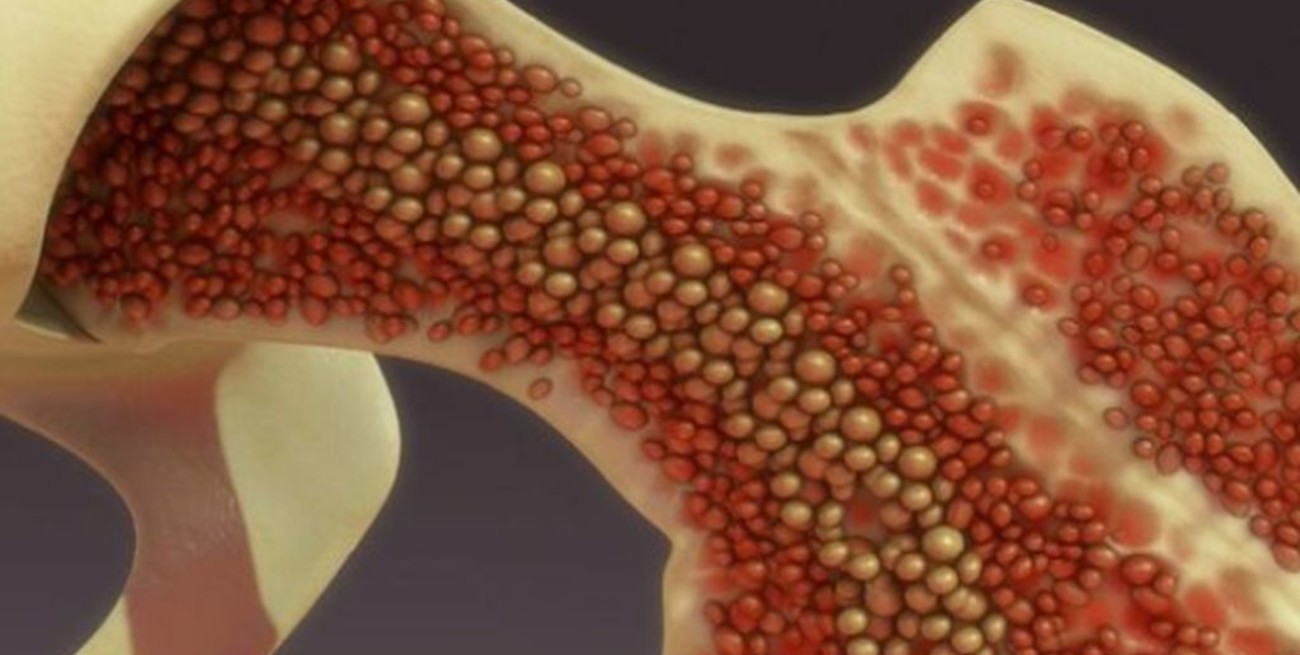

La activación de la médula ósea podría tener un papel fundamental en el origen y desarrollo de las aterosclerosis, el proceso subyacente en muchas de las enfermedades cardiovasculares

Identificar la ateroesclerosis de forma temprana, permitiría mejorar la salud de millones de personas. Esta nueva investigación publicada en la revista European Heart Journal, sugiere que un camino puede ser estudiar el papel de la médula ósea, que se activa en respuesta a factores de riesgo cardiovascular. Esa activación produce un aumento de células inflamatorias en la sangre, las cuales desencadenan un proceso que daría lugar al inicio y posterior progresión de la ateroesclerosis.

La cardióloga de CNIC Ana Devesa, primera firmante del artículo, explica que los factores de riesgo que producen la activación de la médula ósea son aquellos relacionados con el síndrome metabólico: obesidad central (perímetro de la cintura aumentado), triglicéridos altos, colesterol HDL bajo, glucosa en sangre elevada, resistencia a la insulina y tensión arterial alta.

Estos factores provocan un aumento de la actividad metabólica en la médula ósea que "desencadena un proceso inflamatorio que activa el proceso de aterosclerosis, desde sus fases más incipientes hasta la aparición de la placa establecida”, explica Devesa.